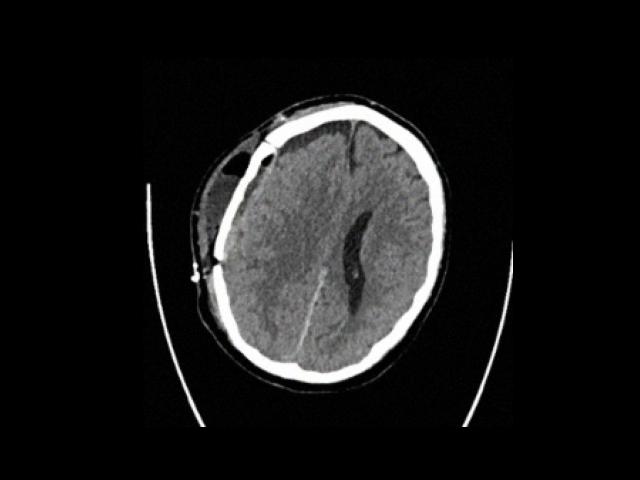

Sample Gallery